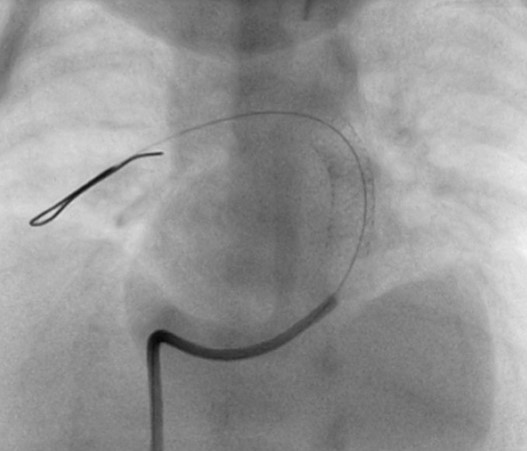

A coronary wire (Wizdom Cordis) is then placed into the distal pulmonary artery. Generally, it goes easiest into the RPA, but either branch is fine. It is important to get it as distal as possible. I then guide the RCA catheter over the wire into the proximal RPA. A second coronary wire for better support (GrandSlam Asahi) is positioned into the RPA and the first wire removed. The guide wire distal soft end will often bend upon itself (Figure 2), allowing support from the wire shaft. A trick to improve wire support is to twist the wire in a clock-wise direction until the soft tip is looped in the lung parenchyma. This will fixate the wire and improve tractability of the stent. (Just remember which way to turned the wire so you can release the tip!).

LAO-cranial. A coronary wire is placed in the distal RPA. Note that the soft distal end has folded into itself to allow more wire shaft in the PA for better support. The wire can also be rotated to embed it into lung tissue for additional support.